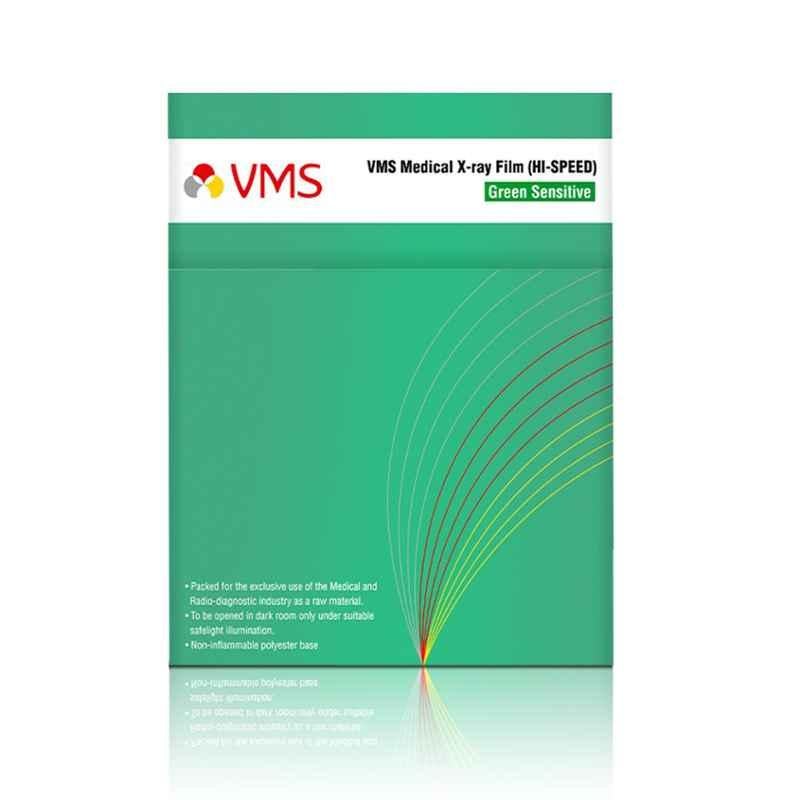

VMS HI-Speed 50 Sheets 12x15 inch Green Base Sensitive Conventional X-Ray Medical Film Set

High Speed Film is Designed for RP Extended & Manual Processing, Developers & Fixer Processing Solutions are Recommended.

Easy to Read, Nice Neutral Look, the Use of a Deep Polyester Base Results in Images with a Nice.

Safelight Requirements the Use of a Special Red Safelight Filter is Recommended, It Should Be Utilized in Conjunction with a 15W Frosted Bulb & Be Positioned at Least 1.2m 0 Feet.

Unopened, Unexposed Film Should Be Stored at or Below 21 deg C in a Dry Location, Relative Humidity is Preferably Between 30-50%, In Addition, the Film Should Be Protected Horn Ionizing Radiation.

Introducing the VMS Hi-Speed 50 Sheets 12x15 inch Green Base Sensitive Conventional X-Ray Medical Film Set, a must-have product in the Medical Accessories category. This high-quality film set, offered by the renowned brand VMS, ensures exceptional image clarity and accuracy. With its uncoated paper finish, this film provides a natural, non-reflective surface, resulting in precise and reliable diagnostic readings. The green base color enhances the visibility and contrast of x-ray images, facilitating effortless interpretation for medical professionals. Each set contains 50 sheets of 12x15 inch film, offering an ample supply for medical facilities. With the model name Hi-Speed, this product guarantees swift image development, saving valuable time in critical medical scenarios. Upgrade your medical imaging procedures with the VMS Hi-Speed 50 Sheets 12x15 inch Green Base Sensitive Conventional X-Ray Medical Film Set.